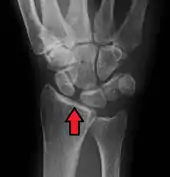

X-ray images indicate scapholunate ligament instability when the scapholunate distance is more than 3 mm, which is called scapholunate dissociation.[7] A static scapholunate instability is generally readily visible, but a dynamic scapholunate instability can only be seen radiographically in certain wrist positions or under certain loading conditions, such as when clenching the wrist, or loading the wrist in ulnar deviation.[6]

In order to diagnose a SLAC wrist you need a posterior anterior (PA) view X-ray, a lateral view X-ray and a fist view X-ray.[8] The fist X-ray is often made if there is no convincing Terry Thomas sign. A fist X-ray of a scapholunate ligament rupture will show a descending capitate bone. Making a fist will give pressure at the capitate, which will descend if there is a rupture in the scapholunate ligament.